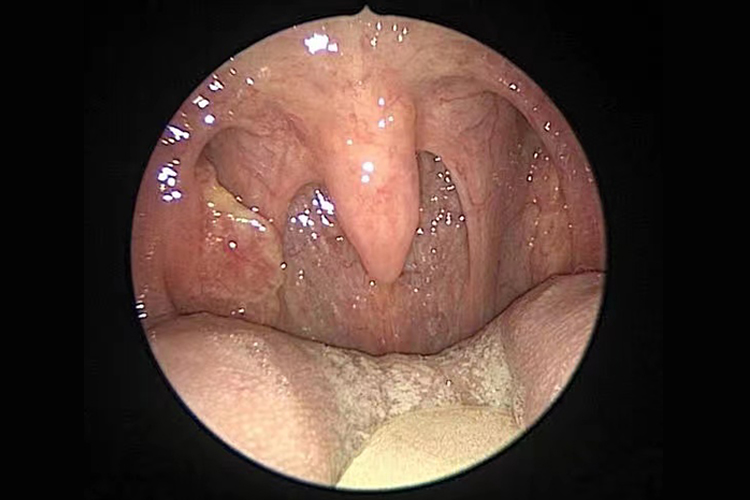

扁桃体表面可出现光滑、淡红色的新生物,多为椭圆形,大小不一,质地较软,常有蒂与扁桃体相连,多无明显自觉症状,若息肉较大,可出现咽部不适。

扁桃体乳头状瘤:主要表现为扁桃体表面的颗粒状或桑葚状肿物,呈白色或粉红色,多数基底部有蒂,直径3-5mm,发展慢,有时呈簇状多发。

扁桃体癌:早期无任何症状,随病情进展可表现为咽部异物感和咽下疼痛,常有口臭、出血及张口困难。查体可见一侧扁桃体肿大,可呈结节状、菜花状,或有溃疡,易出血,常呈外突型鳞癌,易向上颈部淋巴结转移。